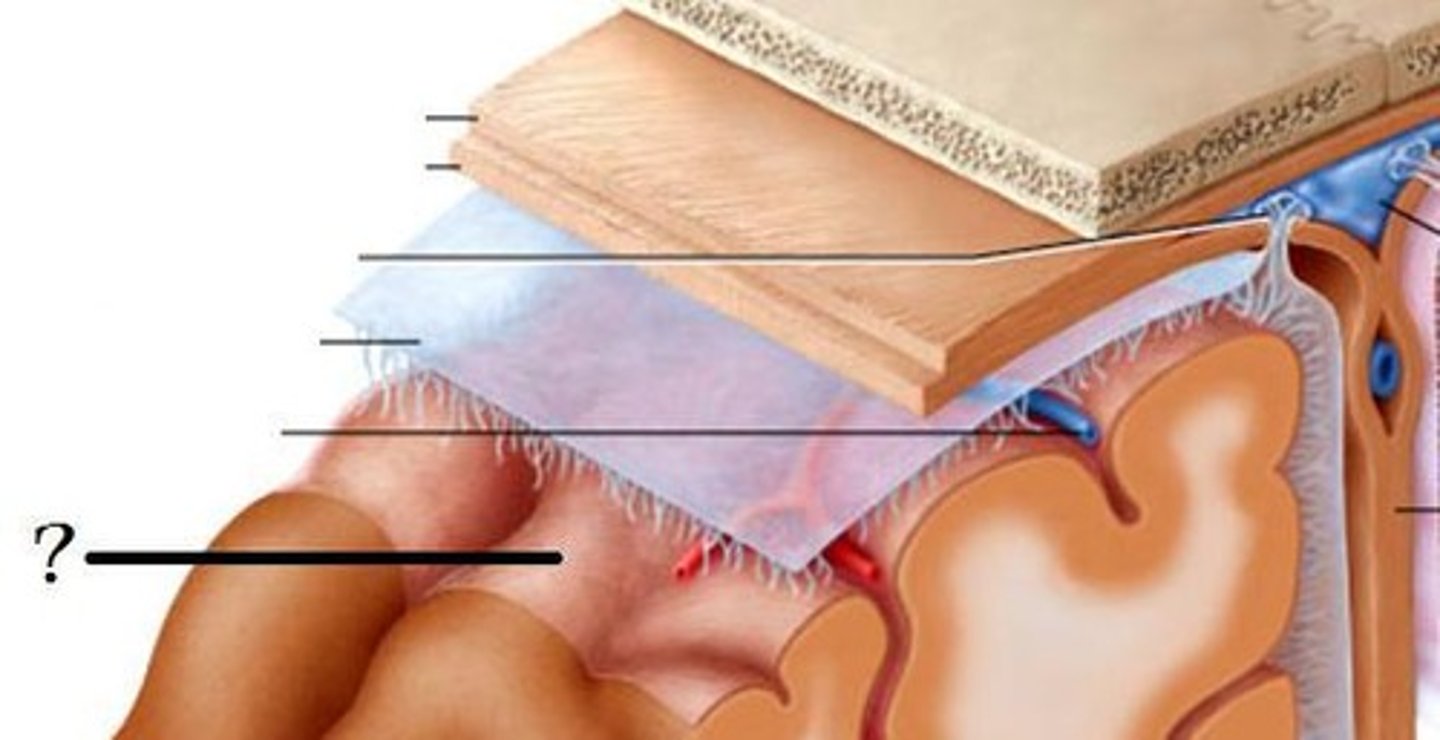

3 layers make up the meninges

dura mater, arachnoid mater, pia mater

arachnoid

middle layer of meninges; weblike appearance that attaches it to deepest layer

arachnoid trabeculae

subdural space

space between dura mater and arachnoid mater

subarachnoid space

arachnoid mater

pia mater

the delicate innermost membrane enveloping the brain and spinal cord.

leptomeninges

The pia mater and arachnoid together